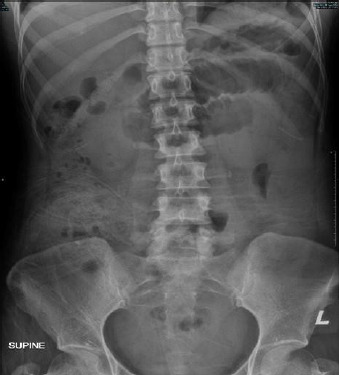

尿淀粉酶水平通常用于诊断急性胰腺炎。不过,也有报告称,没有胰腺炎的人尿淀粉酶水平也会轻微升高。在此,我们报告了一位年轻女士的病例,她因急性腹痛 3 天而就诊。入院时她的尿淀粉酶水平为 1717 U/L,她的病情最初被当作急性胰腺炎治疗。不幸的是,24 小时后患者出现腹部不适,因此紧急进行了计算机断层扫描(CT)检查。CT 显示小肠扩张。她接受了急诊开腹手术,术中发现小肠坏疽,小囊处无皂化迹象。由于高淀粉血症的非特异性,如果临床症状不能提示胰腺炎,或者尽管采取了保守治疗但病情仍恶化,则应考虑急性胰腺炎以外的其他诊断。

Urine amylase levels are usually used to diagnose acute pancreatitis. However, there are reported cases where urine amylase levels are slightly increased in individuals without pancreatitis. Herein, we report the case of a young lady who presented with acute abdominal pain for 3 days. Her urine amylase level was 1717 U/L upon admission, and her condition was initially treated as acute pancreatitis. Unfortunately, the patient demonstrated abdominal guarding after 24 h; thus, urgent computed tomography (CT) was performed. CT revealed the presence of a dilated small bowel. She underwent emergency laparotomy, wherein a gangrenous small bowel with no evidence of saponification at the lesser sac was noted. Due to the non-specific nature of hyperamylasaemia, an alternative diagnosis other than acute pancreatitis should be considered if the clinical symptoms are not suggestive of pancreatitis or the condition worsens despite conservative management.